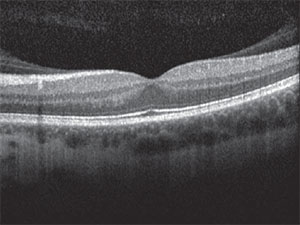

| Figure 2. Optical coherence tomography of the left eye showed vitreomacular adhesion. |

The risks, benefits, and alternatives to various treatment strategies were again discussed with the patient. We also asked her to seek a second opinion with another respected retina expert, which she did. Given her young age, occupation requiring stereopsis, phakic status, history of refractive surgery and vitreomacular adhesion as seen on optical coherence tomography (Figure 2), we offered her primary scleral buckle.